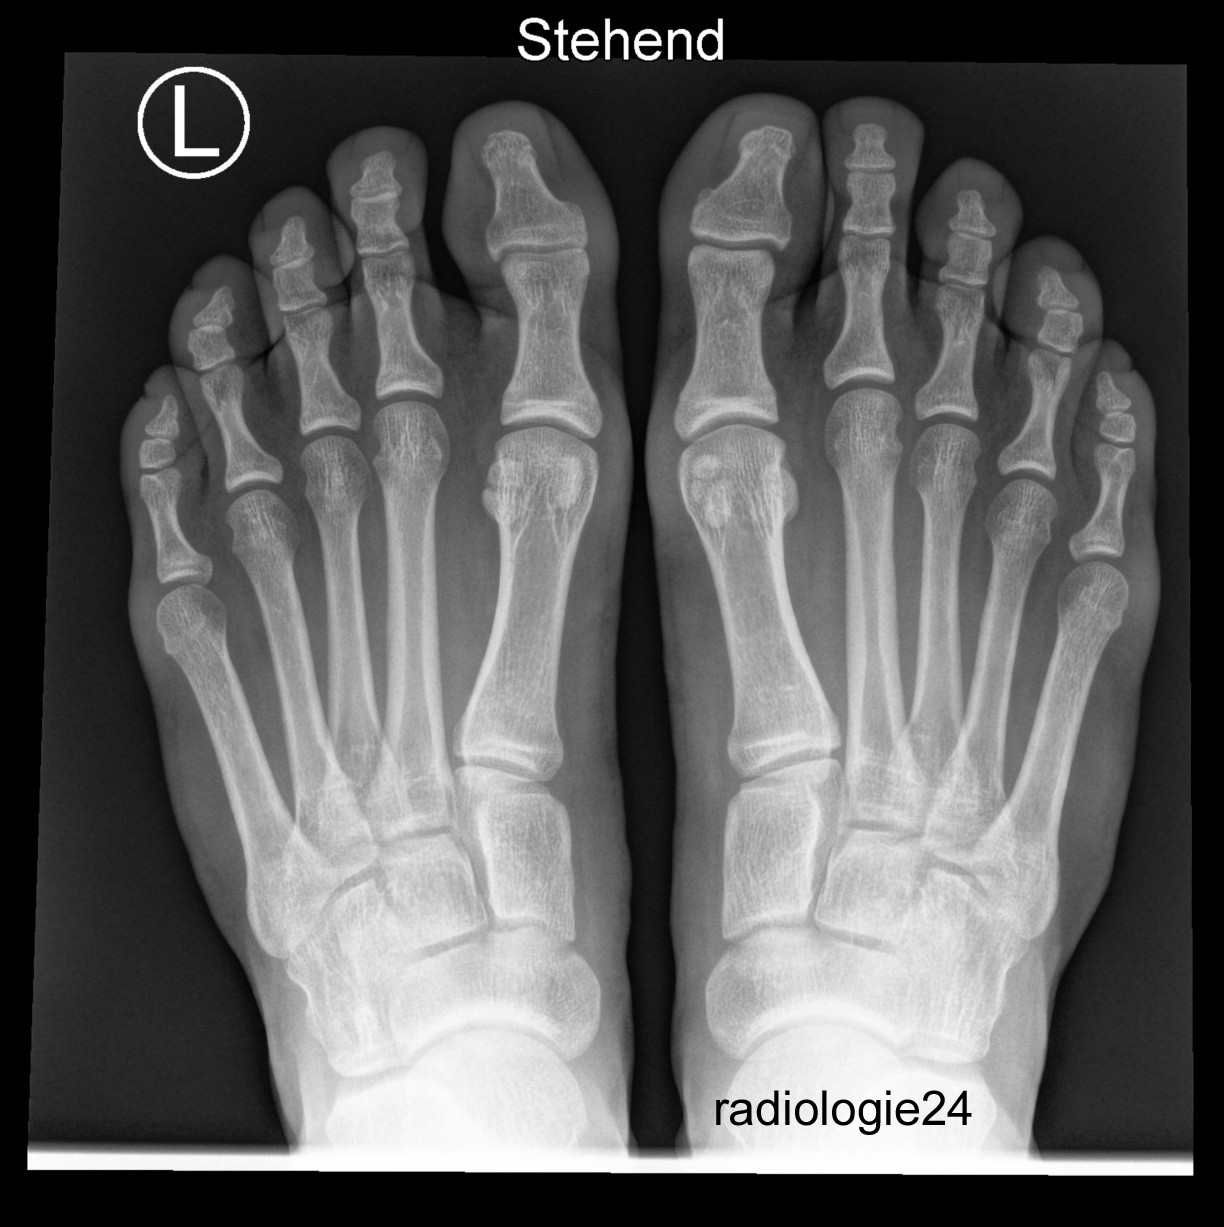

Röntgenfall des Monats November 2018

18 jähriger Patient. Schmerzen im Bereich der Vorfüsse bds. Ihre Diagnose? Weitere radiologische Diagnostik notwendig?